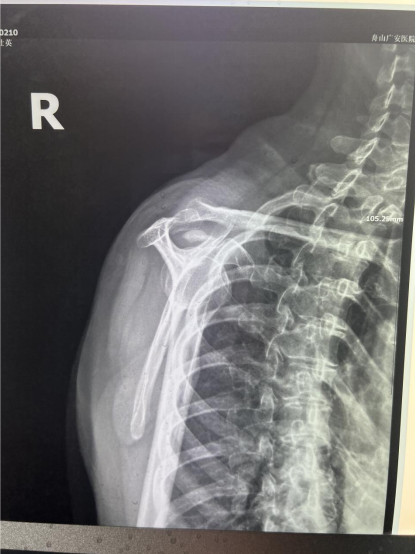

賀大媽慕名來廣安醫(yī)院找羅軍主任就診,面對羅醫(yī)生,賀大媽哭訴:“羅醫(yī)生,我真想剁下自己的這只胳膊。”羅軍主任根據(jù)患者的癥狀拍片,診斷為岡上肌鈣化性肌腱炎,隨后,羅醫(yī)生為李大媽進(jìn)行了肩關(guān)節(jié)鏡微創(chuàng)手術(shù),竟從她的右肩“擠”出“牙膏”。

是不是只要病人撐得住,讓鈣鹽吸收就沒事了?羅軍主任表示,經(jīng)保守治療無法緩解或病程長的患者,應(yīng)盡早采取手術(shù)治療。而且,部分患者鈣鹽無法完全吸收,拖下去只會使病情惡化,造成肩膀肩袖肌腱的損傷。

羅軍主任表示,很多人會把肩痛都?xì)w因于肩周炎,這是一個很大的誤區(qū)。其實,肩痛人群中只有15%左右是肩周炎,大部分肩膀疼痛由于肩袖損傷、肩峰撞擊征、鈣化性肌腱炎。而大多數(shù)人也因此認(rèn)為忍一忍就會自愈,常常延誤治療,關(guān)節(jié)鏡微創(chuàng)治療鈣化性肌腱炎,可以快速緩解疼痛,同時可以修復(fù)肩袖損傷,清理肩膀骨刺。